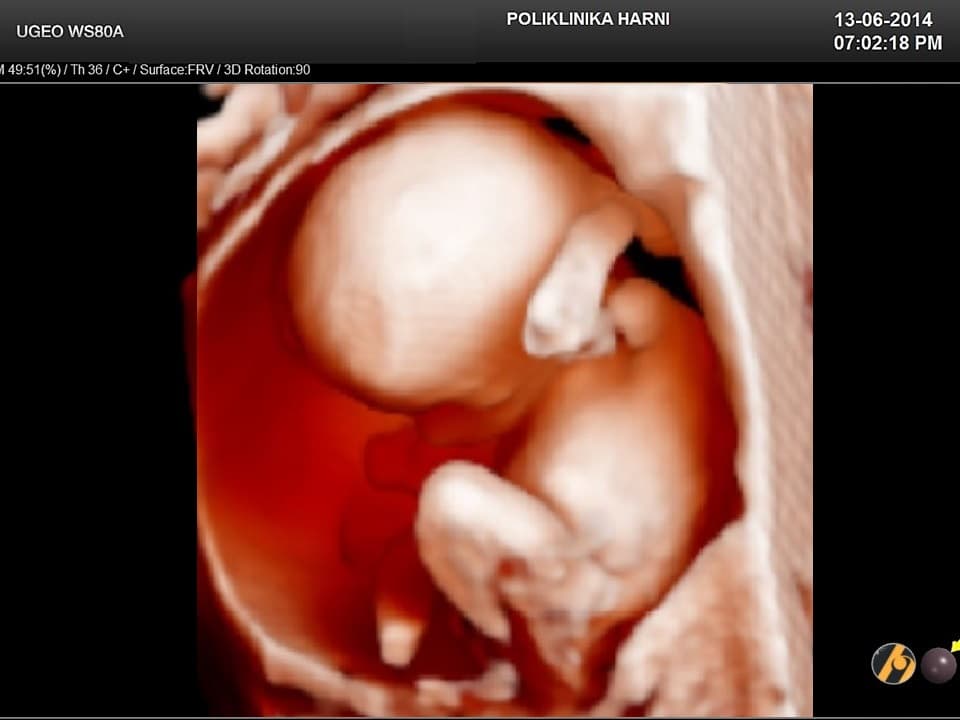

Zahvaljujući intenzivnom razvoju mišića i kostiju, sve su češći fetalni pokreti. Beba uspravlja glavu, ali može i žmirkati, otvarati usta ili se mrštiti jer napreduje i razvoj muskulature lica. Trudnica koja je već rađala počinje osjećati fetalne pokrete u ovom tjednu, dok trudnice koje su po prvi puta ostvarile trudnoću počinju osjećati fetalne pokrete kasnije, obično u 20.tjednu. Fetalne pokrete kasnije osjećaju i trudnice s viškom kilograma, pošto masno tkivo djeluje kao izolator.

Vaša beba dugačka je sveukupno 14 - 16 cm, a teška 80 - 120 g, često se uspoređuje s veličinom avokada.